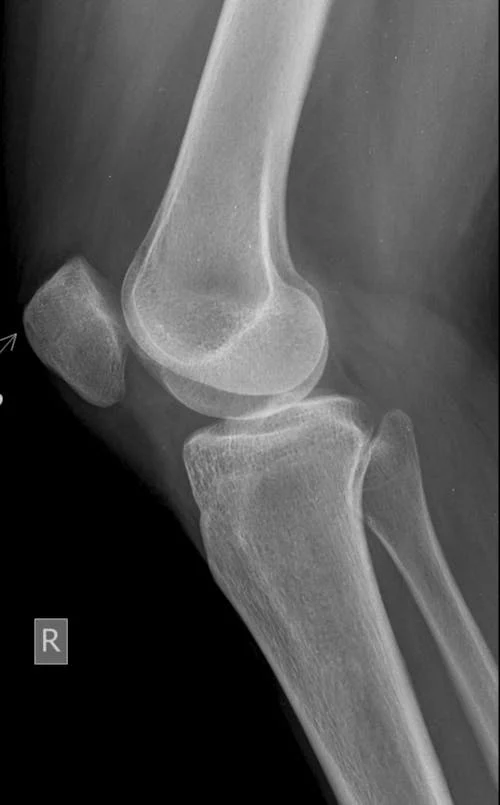

1️⃣ 연골 손상 및 퇴행성 변화

- 무릎 연골이 닳거나 약해진 상태

- 초기에는 평지 보행은 괜찮음

- 계단이나 내리막에서 통증 먼저 나타남

4️⃣ 반월상연골 손상

- 무릎 안쪽 또는 바깥쪽 통증

- 계단 내려갈 때 통증 심화

- 무릎이 걸리는 느낌, 소리 동반 가능